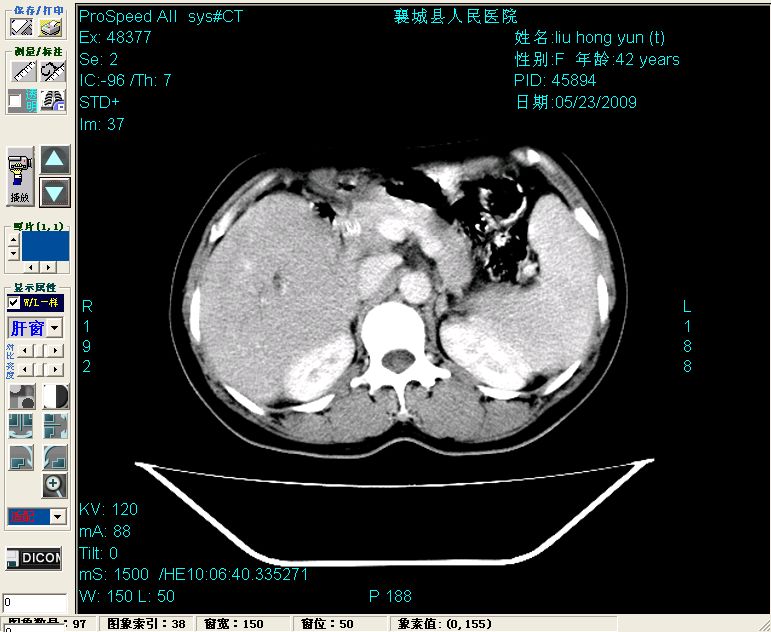

增强:

增强动脉期前述低密度区轻度早其强化,门脉期强化程度显著增高,延期扫描强化程度下降,但仍为相对高密度影

胰头部见结节状高密度影,其前方略可分辨扩强胆部管,平扫到增强始终有,但现在尚难与胃肠造影剂鉴别.

结合病史考虑,1现在引起黄疸体征的原因应该是胆总管胰段结石阻塞,建议局部胃肠造影剂排空后复查.

2左肝及右肝前叶表现考虑胆囊摘除术后所致的肝动门脉瘘形成,慢性纤维组织炎性增生.不完全除外左肝胆管细胞癌